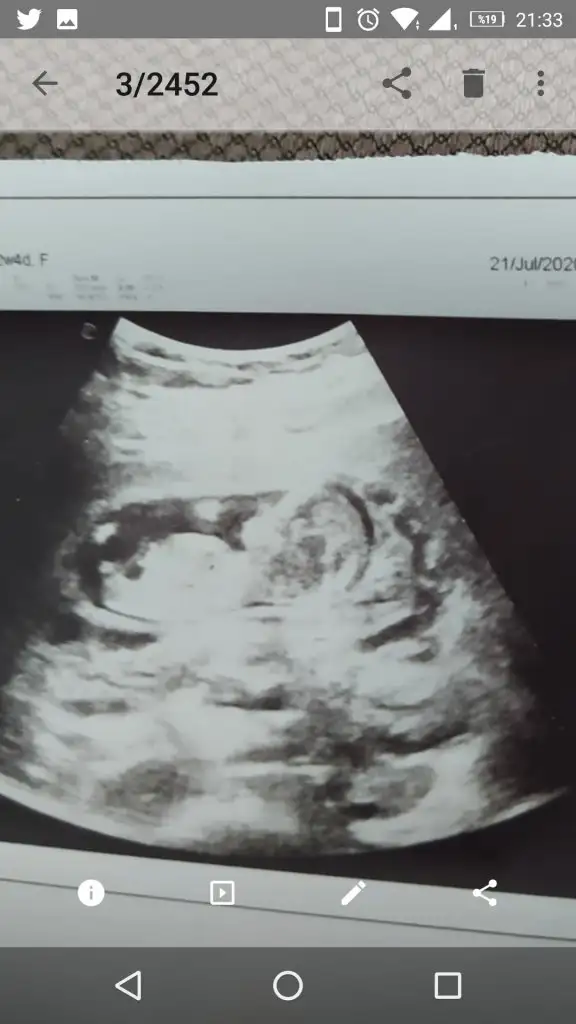

Kız sanki emin olmadım çok net değil usg varsa 11 yada 13 hafta usg olursa paylaşınSelam canlar, anlayan varsa bize de bakabilir mi acaba

Sadece resmi paylaşın tahminini yazmayın bakalım tutturacammıTeşekkürler2 hafta sonra randevumuz var doktorun tahmini olursa burda resmî ve tahmini de paylaşıcam

Tamam anlaştıkSadece resmi paylaşın tahminini yazmayın bakalım tutturacammı